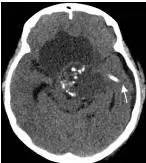

病例二:患儿女性,7岁,主因头痛2年,精神差1个月收入院。入院时头CT见典型的“超大型”颅咽管瘤,直径约9厘米,见图6。

图6.CT显示囊性颅咽管瘤

白色三角显示肿瘤边界